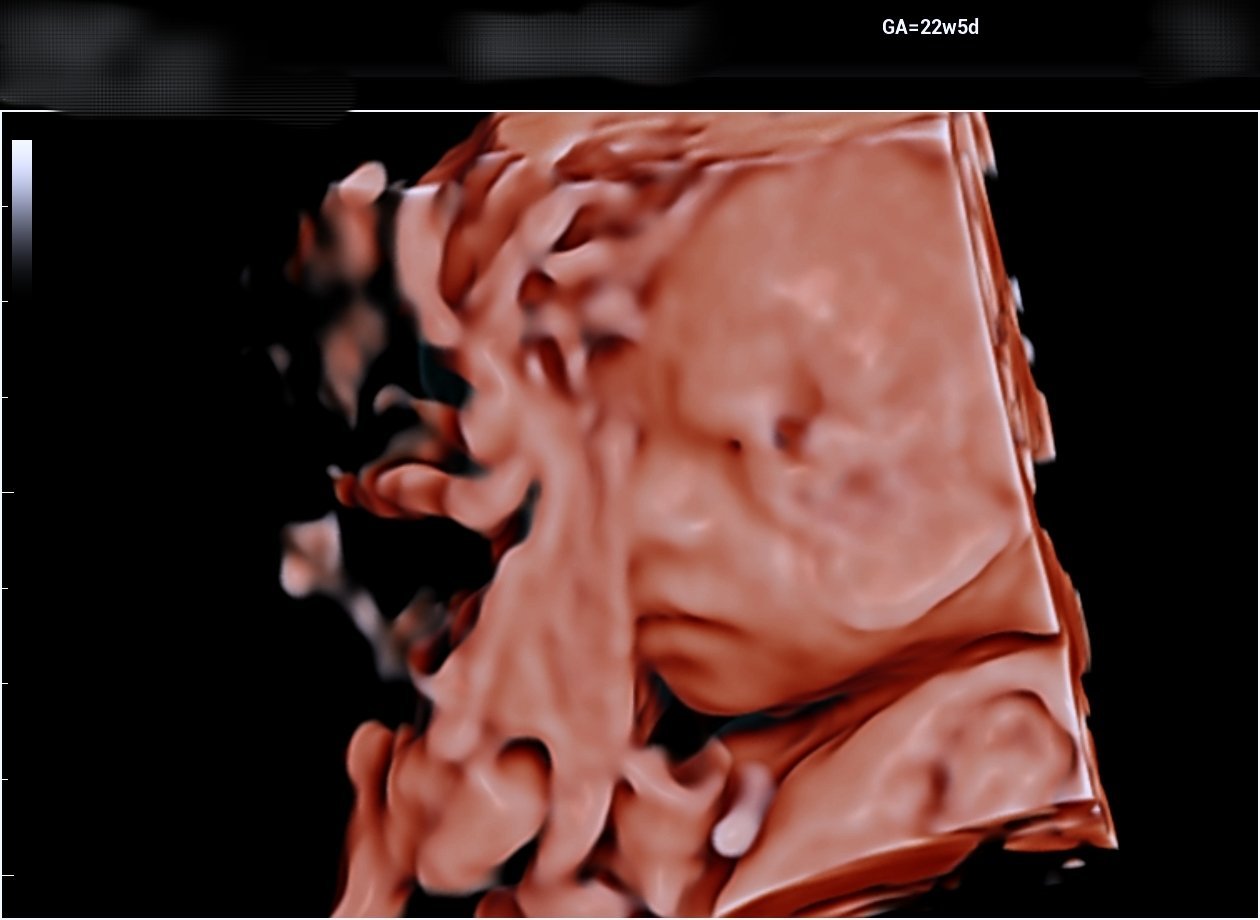

Здравейте момичета! И моята фетална морфология мина днес в 22+5г.с. съм., всичко е наред прегледа продължи около 45-50 мин. гледаха я много обстойно и лекаря каза, че всичко е перфектно. Тежи 550гр. 🩷 Прегледа ми струваше 170лв и бих искала да ви запозная с малката ми Селина 🩷🎀